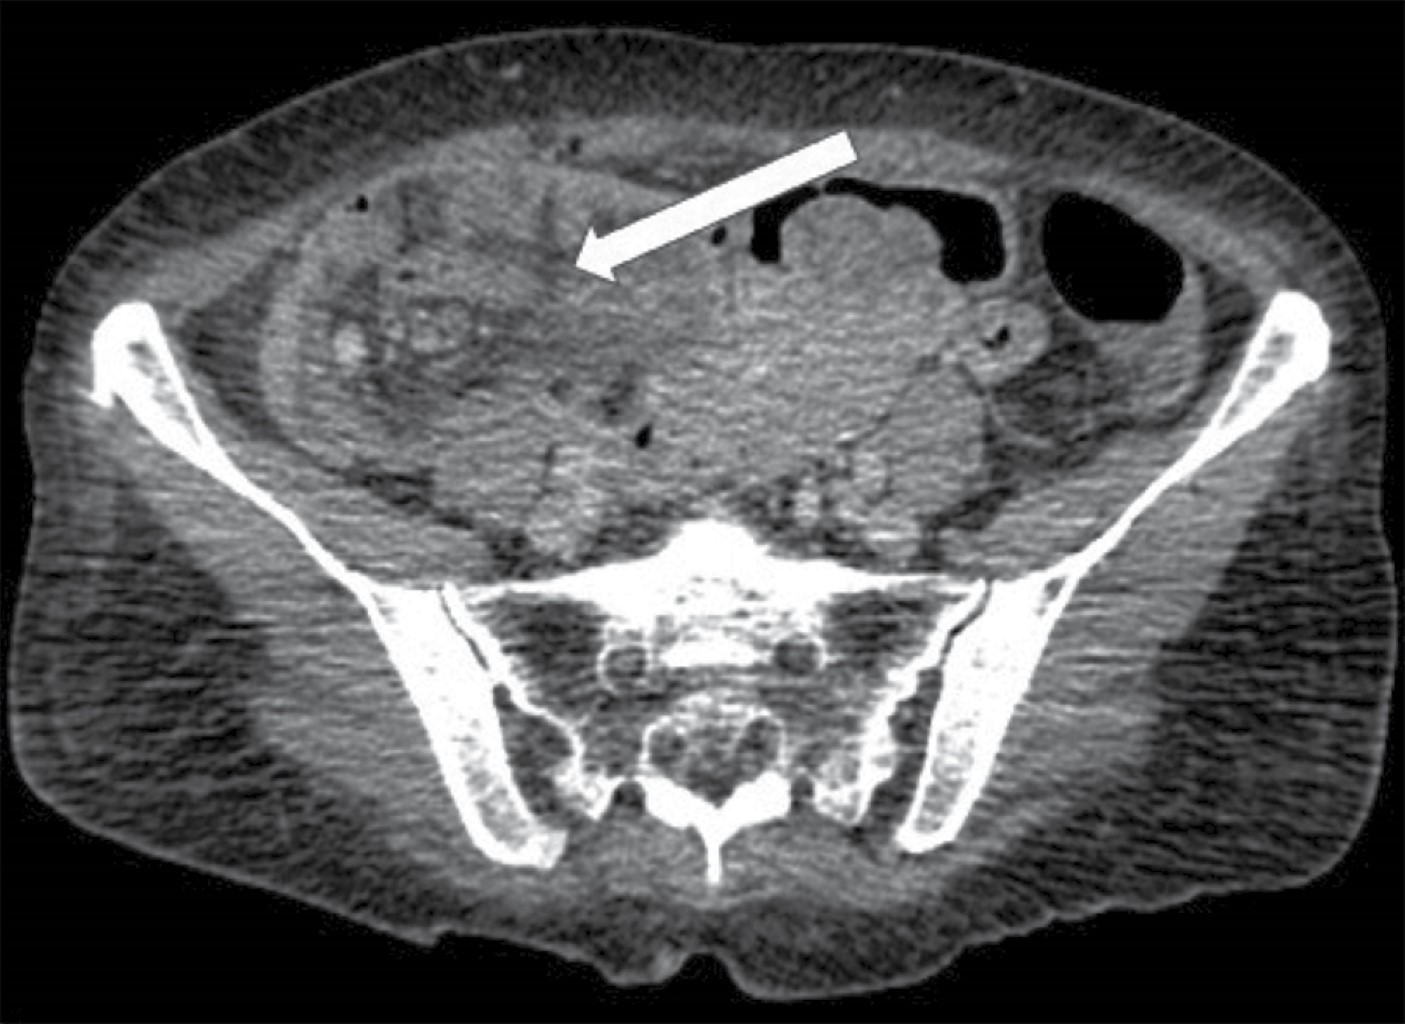

Figure 2